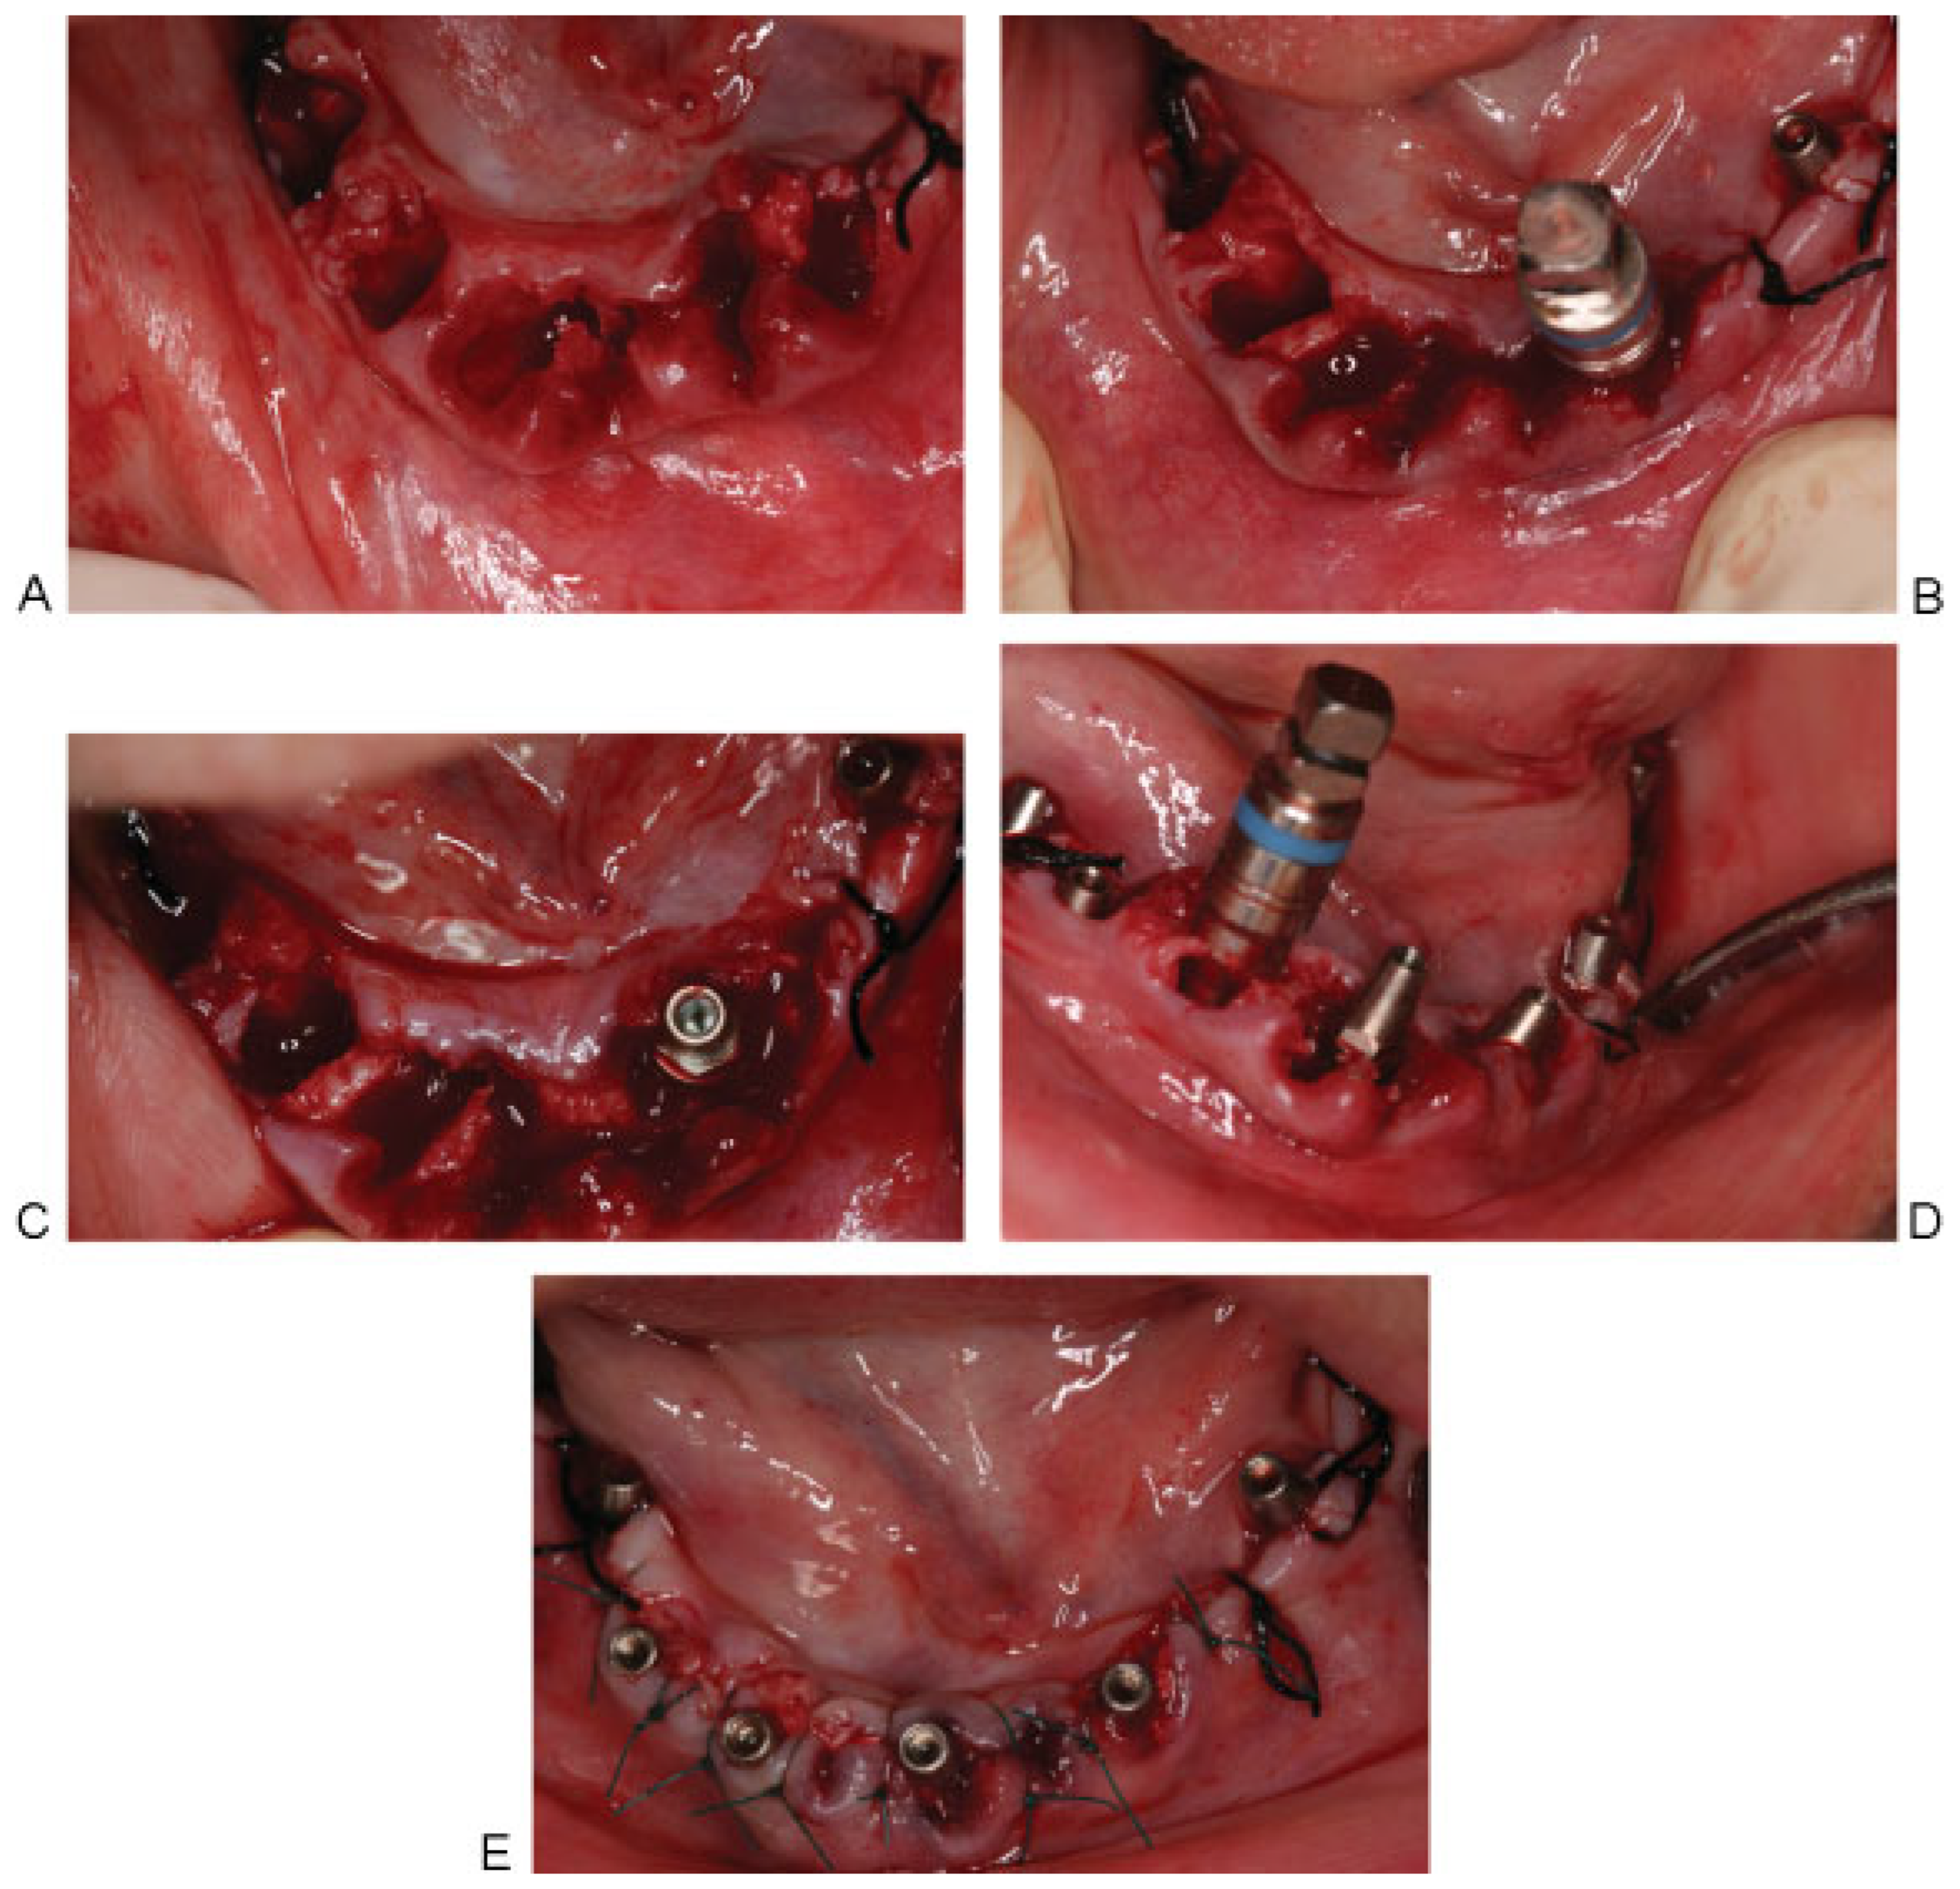

Bilateral IAN block anesthesia was then given to the patient and atraumatic simultaneous extraction of the anterior teeth was performed. Four 3.85-mm width MRT postextraction implants were inserted (two implants of 12-mm length and two implants of 14-mm length) (Figure 5).

Figure 5. (A) Atraumatic extraction of the six anterior teeth followed by curettage of the sockets and removing any bony spicules using bone rongeur. (B) Drilling 3 mm in the depth of the lingual wall using pilot drill followed by threaded bone expander no. 2 to allow for bone condensation against the walls of the osteotomy, which aids in better implant stability and positioning the implant buccally without compromising esthetics. (C) MRT implant in place. (D) Continue the same procedure in other sockets. (E) Four postextraction MRT implants and positioning back the flap.